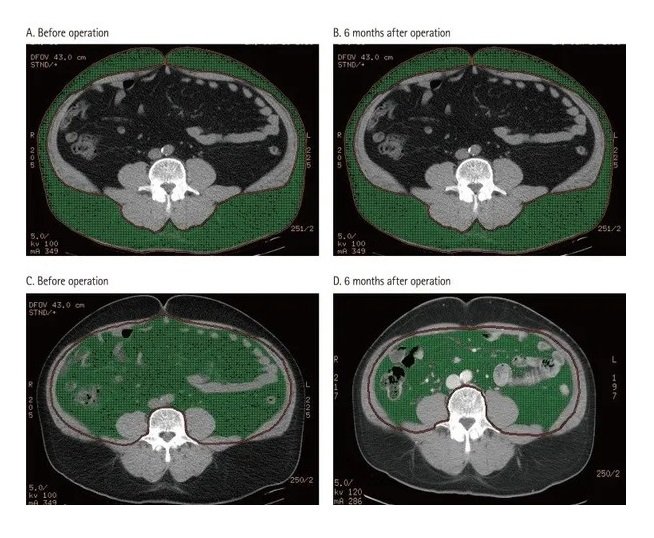

This shows just how fast Visceral Fat is eliminated by simply cutting out PROCESSED FOODS from your diet! In this case series this 68-year-old male client just eliminated processed foods and nothing else, turning from a belly bulging 68-year-old to having a waist/abdomen like a collegiate athlete in their twenties. He did NOT exercise ONE MINUTE. Honestly, you are likely wasting your precious time exercising if you are continuing to eat processed foods. I scan clients to show what really matters - their visceral fat! After showing them their own visceral fat, I provide every client with over 40 strategies to eliminate it and with it their chronic disease.

This is a before and after photo in this 63-year-old client showing his improved abdomen in just 5 months after following the 40 strategies developed for the National Science Foundation to reverse chronic disease. His abdominal scans are directly below:

Shown in the image on bottom is an initial MRI scan showing massive amounts of visceral fat. The top image shows reduced Visceral Fat after following strategies seen in repeat follow-up scan five months later.